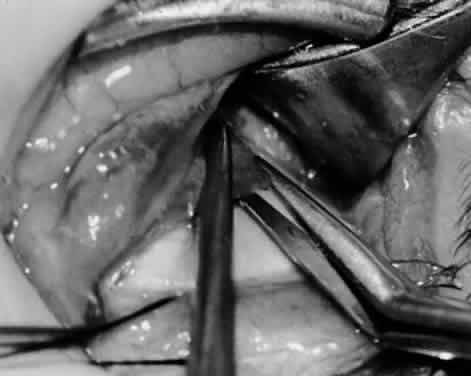

Fig. 11. Sutures are placed into the insertion of the inferior oblique muscle before it is sectioned from the globe for the recession procedure.

Fig. 12. An Aebli scissor is placed beneath the inferior oblique muscle insertion before it is sectioned from the globe.

Fig. 13. The inferior oblique muscle is sectioned from the globe. A preplaced 6-0 Vicryl suture is attached to the insertion.

Fig. 14. The inferior temporal vortex vein, 8 mm posterior to the temporal insertion of the inferior rectus muscle, is held on a Green muscle hook.

Fig. 15. The placement of sutures within the sclera for a recession procedure of 10 mm. The anterior suture is placed 3 mm temporal and 2 mm posterior to the lateral insertion of the inferior rectus muscle, and the posterior suture is placed 3 mm further posteriorly.

Fig. 16. Two sutures straddle the inferior temporal vortex vein insertion for a 14-mm recession procedure.

Fig. 17. Knots are tied to show the placement. The inferior oblique muscle is held on a Stevens muscle hook.

Fig. 18. The final position, with the inferior oblique muscle recessed 10 mm. The inferior rectus muscle is retracted with a Green muscle hook. As described in the text, the 14-mm recession would place the inferior oblique muscle over the inferior temporal vortex vein, and the 6-mm recession would place the inferior oblique muscle anterior and nasal to this position.

Fig. 19. A 14-mm inferior oblique muscle recession is placed over the inferior temporal vortex vein.

Fig. 20. Optional closure of the incision with a 6-0 Vicryl suture. The incision may be allowed to heal without a suture.